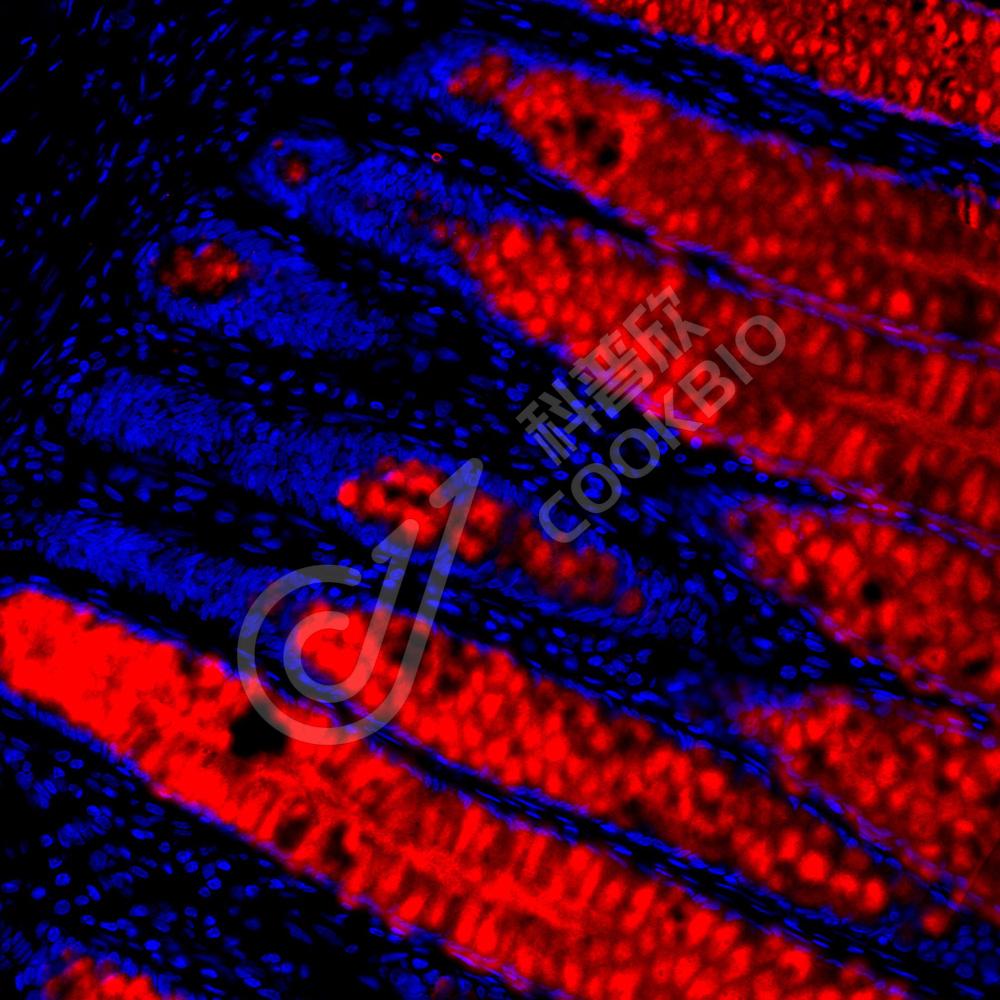

IF检测E-cadherin蛋白(货号 K133246)(红色).

样品: 小鼠结肠, 4%多聚甲醛 (货号KSG1101) 固定12-24小时.

抗原修复: Tris-EDTA抗原修复液(pH 9.0) (KSG1203), 98℃, 20分钟.

封闭: 3% BSA(货号KSGC305010)的PBS溶液, 室温孵育30分钟.

—抗: 1: 900稀释, 4℃ 孵育过夜.

二抗: Cy3标记山羊抗兔IgG (H+L) (货号KB63909), 1: 300稀释, 室温孵育1小时.